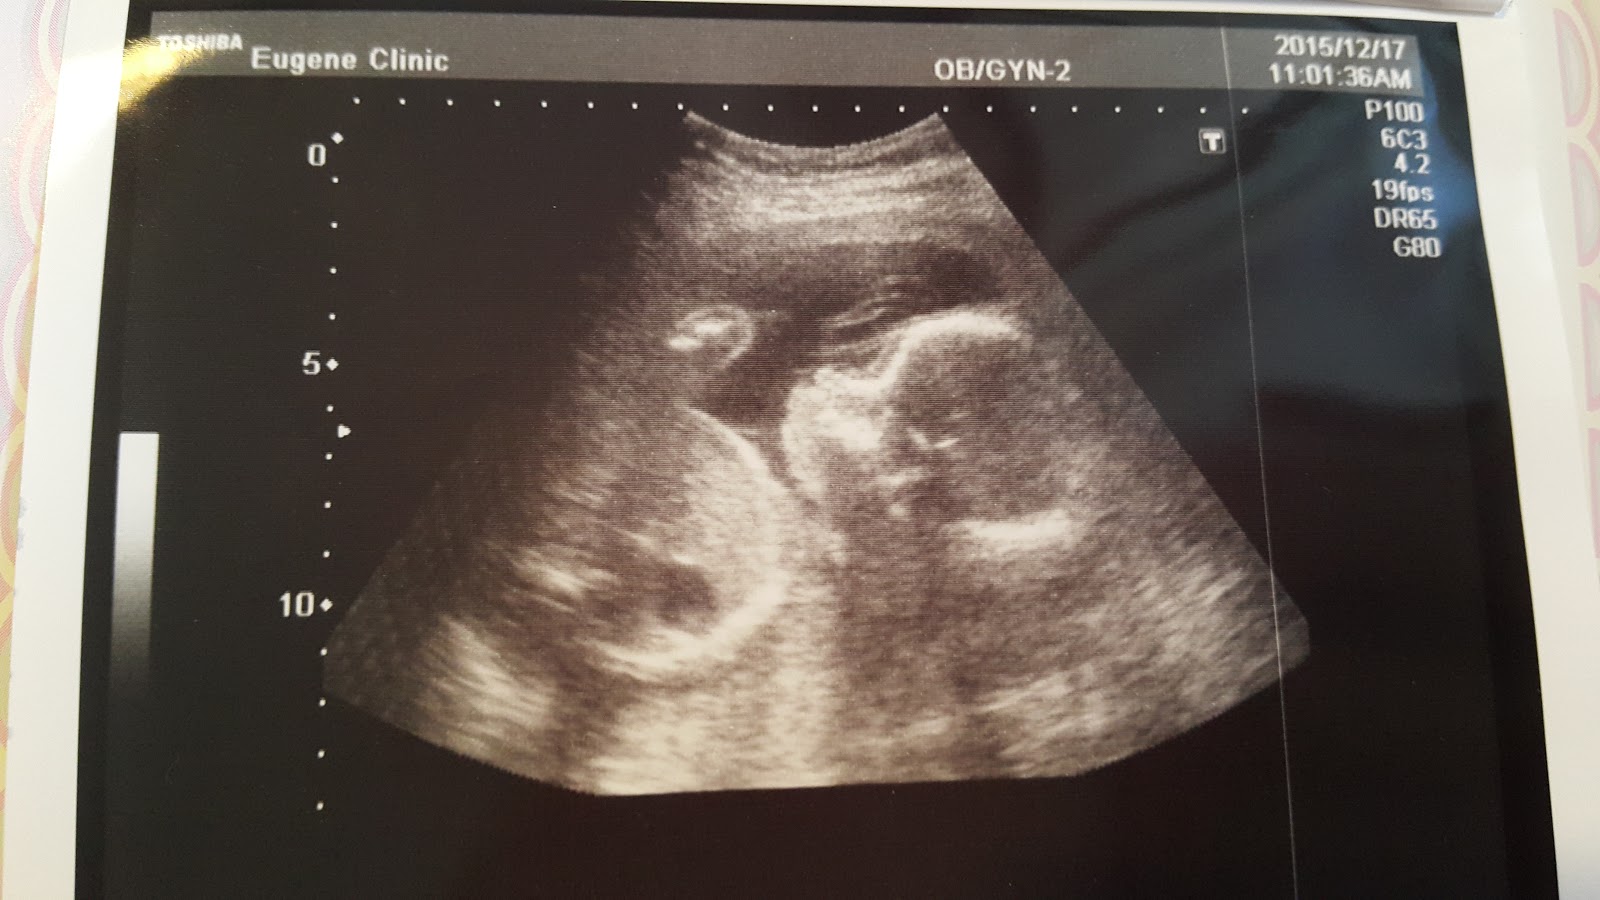

2015年就要過完了,孕期也走到5個月,22週了

Haru現在長大有480g了,有在好好長大

Haru的側面

媽媽覺得很可愛!

整個都是愛心,Haru是枚活潑的小女生

醫生這次照超音波在肚皮上多停留了一下

結束時說,先幫你們看了一下

沒有兔唇!

呼~又一顆大石放下!

5個月的產檢報告到這裡,下星期有高層次超音波等著我